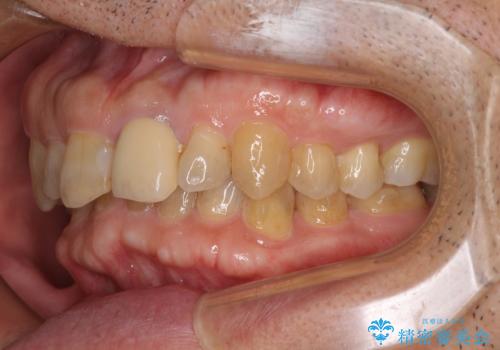

下顎は左右1本ずつ小臼歯が欠損しており、右側にはやや大きな欠損がありました。

欠損により下顎歯列は相対的に小さく、上顎に深く咬みこんでしまうディープバイトとなっていました。

咬合力が強く、インビザラインのみではディープバイトを改善することができず、半年間ほどワイヤー装置による矯正治療を行いました。

インプラントの埋入は矯正治療中に行い、矯正治療後はインプラント上補綴および、前歯のセラミック治療を行いました。